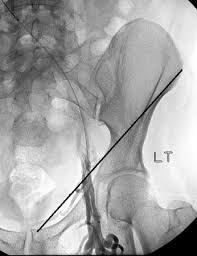

Ligaments Hip Inguinal Ligament Ranzcrpart1 Wiki Fandom

El ligamento inguinal está etiquetado en la parte inferior derecha. Inguinal ligament / poupart's ligament lower border of aponeurosis of ext. The inguinal ligament (also known as poupart's ligament or the fallopian ligament) is a fibrous band extending from the anterior superior iliac spine to the pubic tubercle. Its anatomy is very important for operating on hernia patients. (ligamentum inguinale anlamı, ligamentum inguinale latincesi, latincede ligamentum inguinale, ligamentum inguinale nnd). The inguinal ligament supports the muscles that run inferior to its fibers, including the iliopsoas and pectineus muscles of the hip. Below the fold of groin is where. Among the hypotheses advanced to explain this frequency, the role played by the inguinal ligament was underlined.

Frontolateral view of the right side of the pelvis. The inguinal ligament is a vital connective tissue structure in the inguinal, or crotch, part of the human body. Because of its positioning, the ligament is responsible for helping to support the lower. Estructuras que pasan por detrás del ligamento inguinal. It underpins delicate tissues in the crotch and also the outside stomach angled muscle. Structures passing behind the inguinal ligament. Vista frontal lateral del el punto medio del ligamento inguinal, a medio camino entre la espina ilíaca anterosuperior y el tubérculo púbico, es el punto de referencia del nervio femoral. Poupart's ligament webster's new international english dictionary.